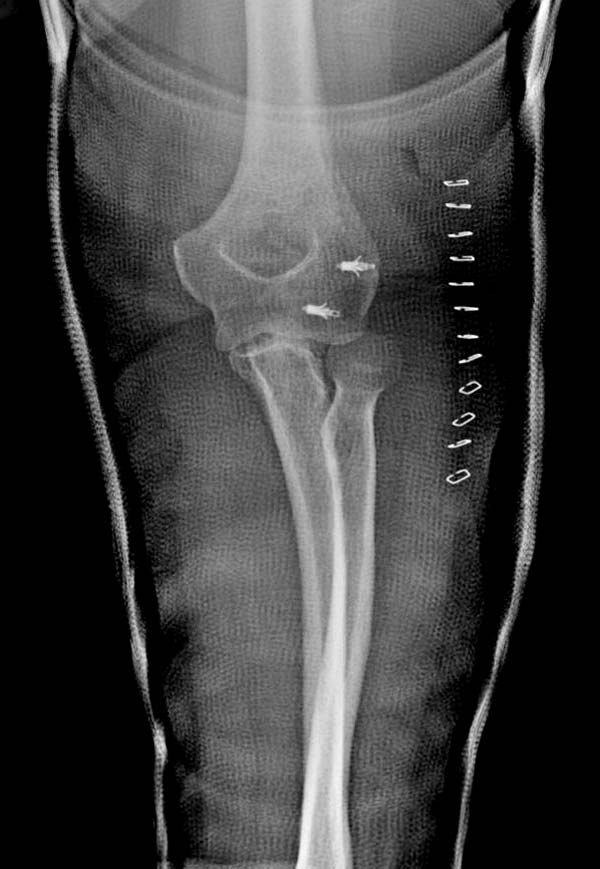

Снимки: 1-2 вывих, 4-5 вторичное смещение в гипсе, реконструкция

латеральной связки и капсулы 13-14, повторный вывих после реконструкции,

перевод в наш центр; 18-21 временная фиксация, 22-25 трансартикулярная

Вложение не в текстовом формате было извлечено…

Имя     : 21 Elbow dislocation closed reduction SLU 6.JPG

Тип     : image/jpeg

Размер  : 37692 байтов

Описание: отсутствует

Url     : http://weborto.net:8080/pipermail/ortho/attachments/20131212/4b05a6a3/attachment-0009.jpeg